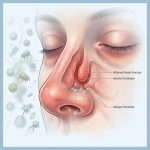

Hubungan Alergi Hidung dengan Kesehatan Paru yang Sering Diabaikan Banyak Orang

infokesehatanhidung.id – Hubungan alergi hidung dengan kesehatan paru ternyata jauh lebih erat dibanding yang dibayangkan banyak orang. Saat hidung terus mengalami alergi, saluran pernapasan bagian bawah juga bisa ikut terdampak tanpa disadari. Itulah sebabnya banyak penderita alergi hidung sering mengalami batuk berkepanjangan, sesak napas, hingga gangguan tidur yang memengaruhi kualitas hidup sehari-hari. Mengapa Alergi Hidung […]